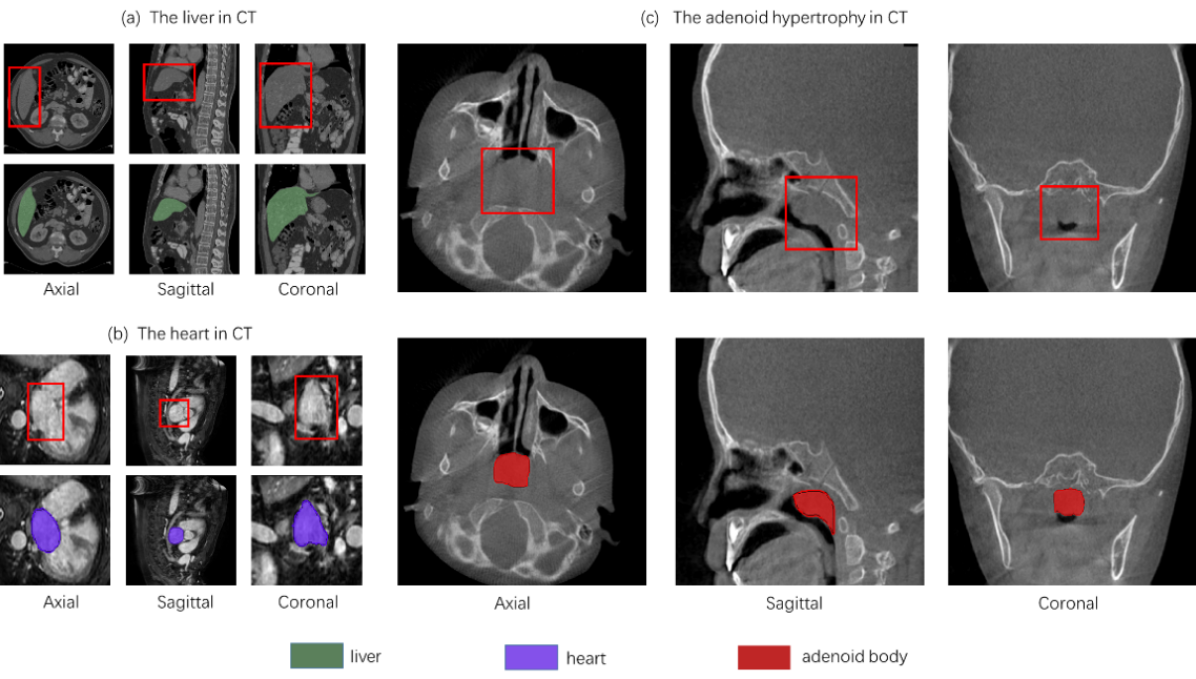

Nonetheless, the segmentation of adenoid hypertrophy encounters challenges that the task deviates from conventional medical 3D segmentation endeavors due to the relatively indistinct nature of its segmentation boundaries. As depicted in Fig. 2, typical segmentation tasks, such as delineating the liver and heart in CT scans, exhibit well-defined boundaries and precise localization. In contrast, the adenoid hypertrophic region in the Axial plane of CT scans presents challenges with less conspicuous segmentation boundaries. The anterior boundary aligns with the posterior edge of the nostril, while the posterior boundary and the delineation of lateral boundaries exhibit ambiguity. In the clinical surgical context, it is imperative to restrict the depth of the posterior border to mitigate the risk of inadvertent damage to the posterior vertebrae, prevertebral muscles, and fascia during surgical ablation. This aspect holds significant clinical relevance to minimize postoperative complications and promote optimal patient outcomes.

Refer to caption

Figure 2: Common segmentation task vs. adenoid hypertrophy segmentation task: Unlike common segmentation tasks, the boundaries of the segmented objects in the adenoid hypertrophy segmentation task are vague and unclear.